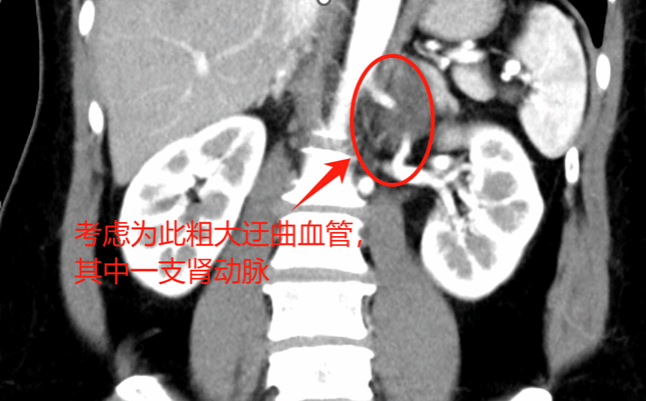

7. 分离顺序:上极→内侧→下极→外侧→向中心。肿瘤上极见多支穿支血管进入肿瘤,其中包括一支粗大血管进入肾脏,复习术前影像,考虑可能为挤压变形的肾动脉,遂保留。

8. 肿瘤内侧紧贴腹主动脉,注意轻柔小心操作。肿瘤后方中心与肾静脉粘连紧密,侵犯可能,分离过程中肾静脉可见破口出血,血液涌出,压迫出血点吸净积血后,用血管阻断夹夹闭肾静脉。

a) 术前细致的影像学评估,判断累及的器官及大血管走向,做到胸中有数。本例虽为神经鞘瘤,增强CT强化不明显 ,但较大肿瘤压迫导致回流不佳形成较多侧支循环,分离时应轻柔精细操作,及时电凝、夹闭或缝扎血管减少出血。肿瘤占位作用也导致正常血管移位(例如上极的肾动脉、肿瘤前上方的肠系膜上动脉),需严格保护。术前需反复阅片。